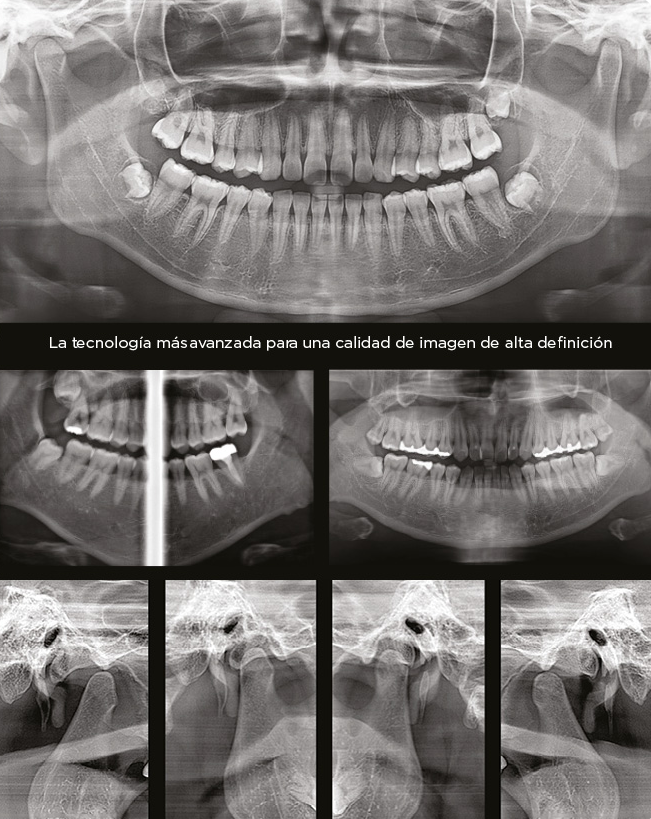

Panorama claro

La tecnología de Enfoque en Movimiento Adaptativo (AMF por sus siglas en inglés) selecciona la capa de imagen óptima para

proporcionar imágenes panorámicas claras, facilitando la identificación de la condición periodontal del paciente y la ubicación

de la lesión.